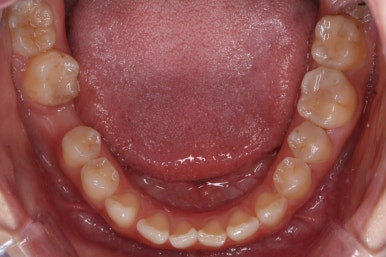

부산부분교정을 하기 전과 후의 모습입니다.

부분교정으로 하였기 때문에 다른 치아의 변화는 전혀 없습니다. 또한 비교적 짧은 기간으로 원하는 목표를 달성했죠.

부분교정으로 매우 만족스러운 결과를 이끌어 냈습니다.